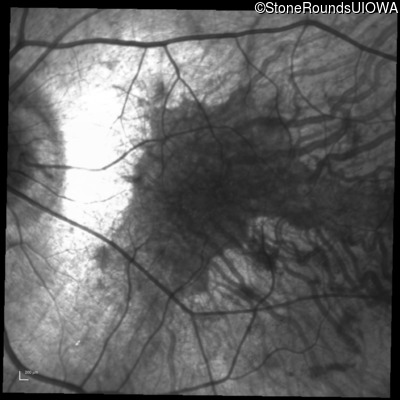

Infrared Fundus Photograph - Right - 20/16

Exemplar